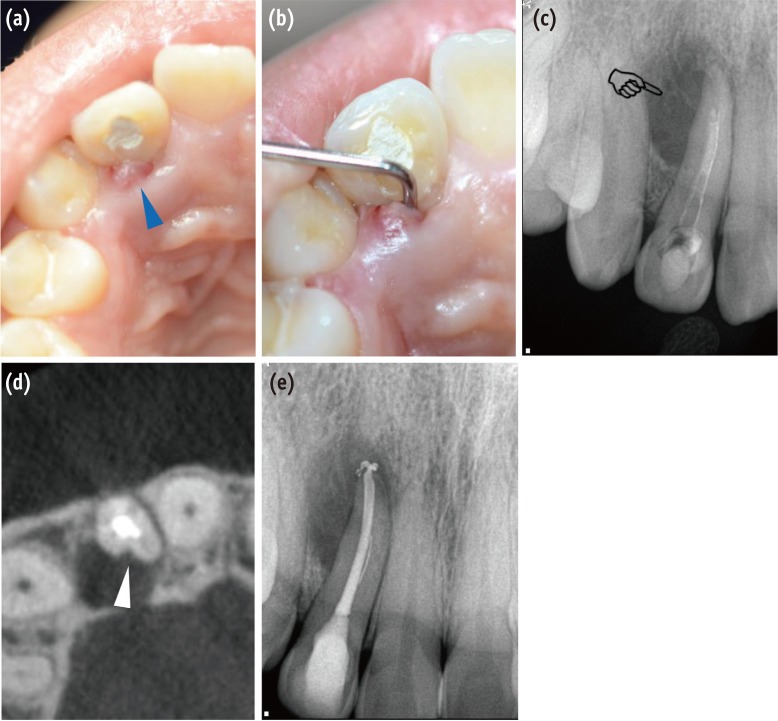

Several PGG cases have been reported recently. Clinically, patients with a pathologic lesion related to PGG often complain of dull intermittent27,28 or acute pain,22,29 mobility of the teeth,30,31,32 pain on percussion,27 pus discharge,29,30,31,33 sinus tract formation (Figure 1a),15,32,33 and gingival swelling.22 They can also present with no symptoms.32 In most cases, the patient had no history of dental caries, trauma, or discoloration of the teeth. Pulp vitality was retained or lost contingent upon pulpal nerve involvement. Cases with advanced lesions along deep grooves frequently show no response to thermal or electric pulp testing.15,22,30,31,32,33,34,35,36 A clinical examination shows funnel-shaped hollow grooves with an accumulation of plaque and calculus, along with loss of epithelial attachment, pocket formation, and bleeding on probing. PGG is often observed bilaterally in the oral cavity. In one study, bilateralism was found in 57.5% of total cases, 63% for coronal and 46.15% for apical grooves among 200 patients.1

Radiographically, teardrop-like radiolucency can be observed in cases with primary pulpal infection,7 and pear-shaped radiolucency (Figure 1c) can be observed in the coronal aspect with apical periodontal widening. In some cases, a radiolucent parapulpal line can be observed as one or more dark lines extending along the length of the root parallel to or superimposed over the root canal.8 In one case report, placement of a gutta-percha cone through the sulcus along the groove could delineate the course and extent of the groove.34 Meanwhile, some authors have indicated difficulties in detecting the groove in conventional radiographs because of overlapping of the structures.37,38 The type of diseases developed from PGG are various: endodontic or periodontal disease or combined endodontic-periodontal disease, resulting in diverse symptoms, including no symptoms even with advanced lesions. It is difficult and simultaneously important to determine the size and location of any bone lesion, the depth and location of the groove onto the root, and the relationship between the lesion and the groove. Three dimensional radiographs using cone beam-computed tomography (CBCT) can provide accurate, sensitive information to assess and plan the treatment of the teeth with PGG (Figure 1d).39 In 2015, Castelo-Baz et al. stated that the information acquired from the CBCT imaging, which showed that the pulp necrosis was not connected to the PGG, is important in making treatment plans, including the choice of an appropriate material to fill the canal.15 However, in consideration of the radiation exposure the patients receive, the use of CBCT should be limited to cases in which conventional imaging fails to provide adequate information.

Figure 1

Clinical and radiographic findings for diagnosis of the periradicular pathosis associated with PGG. (a) A sinus tract was observed on the palatal side of the right maxillary lateral incisor (blue triangle); (b) Deep and narrow pocket depth (> 10 mm) was detected on the palatal side along the root in the vertical direction; (c) A diagnostic periapical radiograph shows pear-shaped or tear-drop-like radiolucency in the coronal aspect of the root apex (pointing finger); (d) A CBCT scan shows a groove with adjacent radiolucency on the palatal aspect of the tooth (white triangle). It is strongly suspected that the pathogen was associated primarily with the PGG; (e) Endodontic treatment was performed to eliminate the possible irritant in the root canal space. PGG, palatogingival groove; CBCT, cone beam-computed tomography.

Figure 1 Clinical and radiographic findings for diagnosis of the periradicular pathosis associated with PGG. (a) A sinus tract was observed on the palatal side of the right maxillary lateral incisor (blue triangle); (b) Deep and narrow pocket depth (> 10 mm) was detected on the palatal side along the root in the vertical direction; (c) A diagnostic periapical radiograph shows pear-shaped or tear-drop-like radiolucency in the coronal aspect of the root apex (pointing finger); (d) A CBCT scan shows a groove with adjacent radiolucency on the palatal aspect of the tooth (white triangle). It is strongly suspected that the pathogen was associated primarily with the PGG; (e) Endodontic treatment was performed to eliminate the possible irritant in the root canal space. PGG, palatogingival groove; CBCT, cone beam-computed tomography.